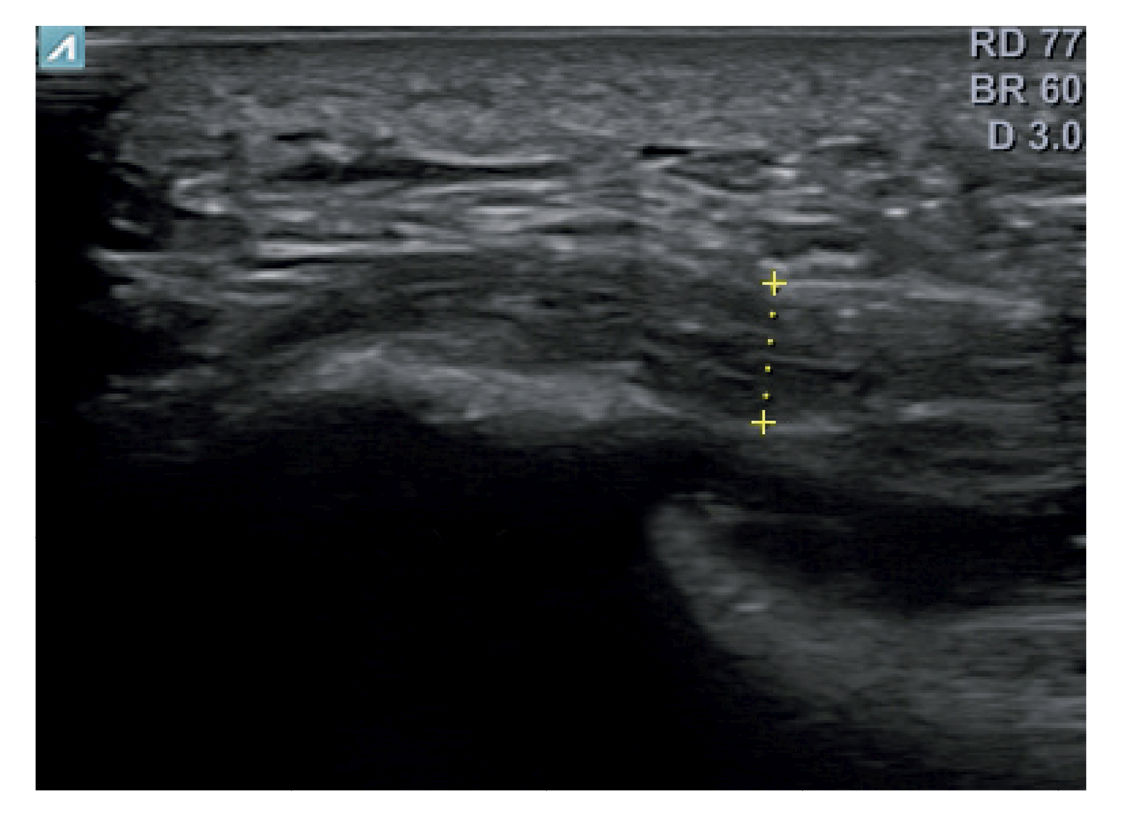

All patients had experienced the classic symptoms of PF, including pain when taking the first steps after waking up or after sitting for a long time. Patients felt pain upon palpation of the proximal plantar fascia and reported that the pain worsened as the day progressed. The diagnosis was established based on symptoms and confirmed by ultrasound using high-resolution equipment (Alpinion Ecube 9, ALPINION MEDICAL SYSTEMS Co., Ltd., Republic of Korea) with a 6-12 MHz linear transducer (Figures 2 and 3).

Figure 2. Researcher with the linear probe for measuring plantar fascia thickness.

Figure 3. Area of measurement of plantar fascia thickness. The dotted line corresponds to the thickness measurement.